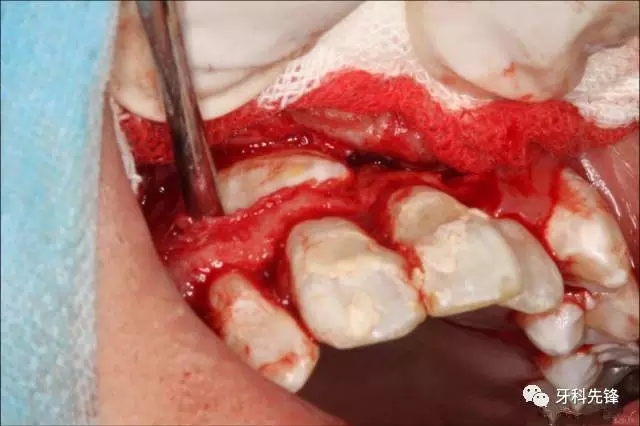

圖6.翻瓣、去骨、暴露13牙冠